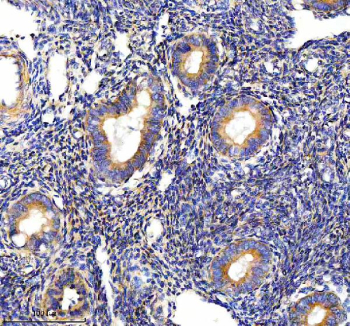

Immunohistochemical staining of PALS1 using anti-PALS1 antibody. PALS1 was detected in a paraffin-embedded section of human endometrial cancer tissue. Heat mediated antigen retrieval was performed in EDTA buffer (pH 8.0, epitope retrieval solution). The tissue section was blocked with 10% goat serum. The tissue section was then incubated with 2 ug/ml rabbit anti-PALS1 antibody overnight at 4oC. Peroxidase Conjugated Goat Anti-rabbit IgG was used as secondary antibody and incubated for 30 minutes at 37oC. The tissue section was developed using an HRP secondary and DAB substrate.